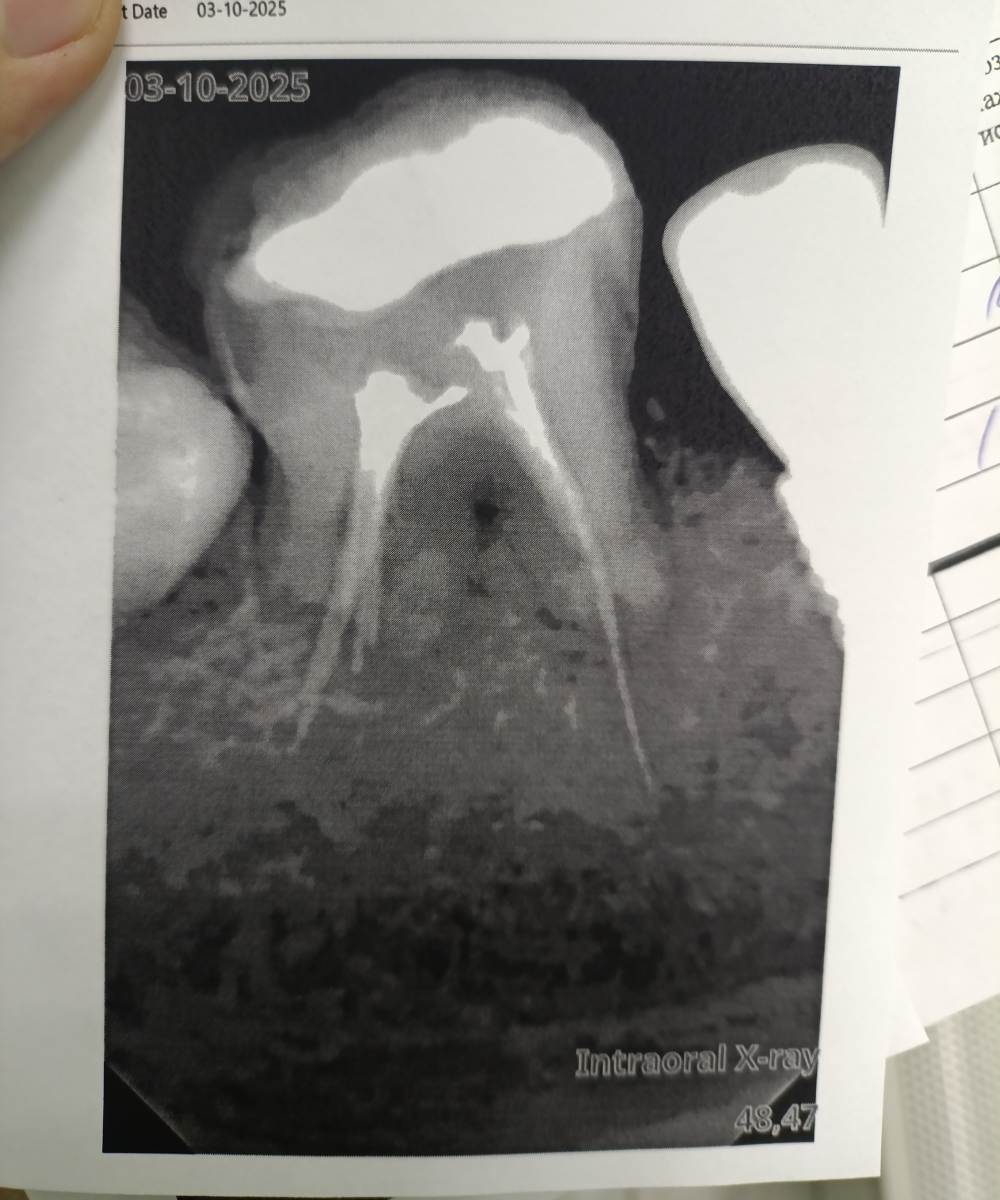

Очаг воспаления между корнями

Добрый день, был глубокий кариес у зуба, начали лечить поставили пульпит. Заложили лекарство, спустя 2 недели боли сохранялись, убрали лекарство, прочистили каналы и запломбировали. Теперь боли полностью ушли, но появляются если дать зубу нагрузку жевательную значительную. То есть если интенсивно жевать на этом зубе, в течение дня начинает нарастать чувствительность зуба (болью не совсем это можно назвать) но на следующий день после сна боль всегда проходит.

Лечение в бесплатно клинике было, поэтому сказали что зуб только удалять, так как воспаление между корнями.

Два снимка с разницей в месяц